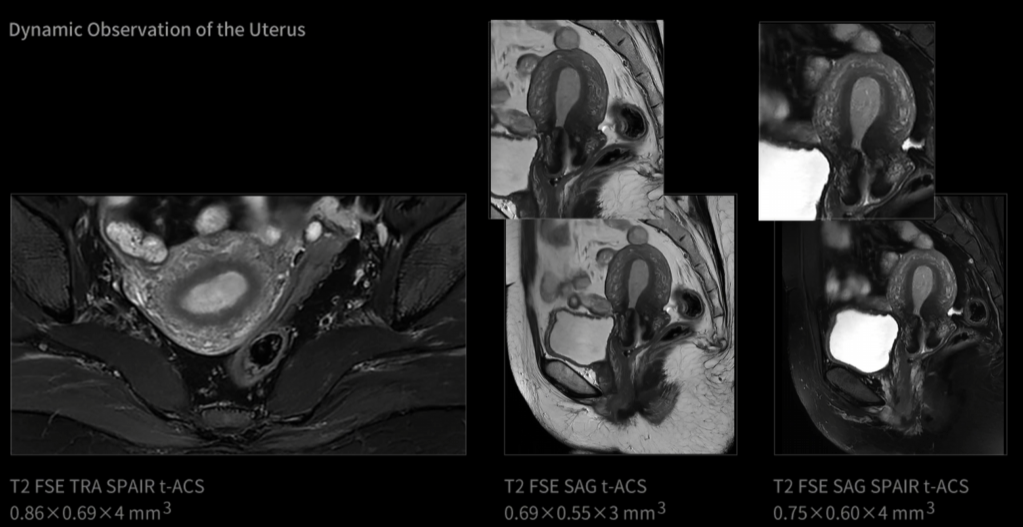

uAIFI.LIVE je nejnovější inovativní platforma, která slouží jako inteligentní řídicí jádro systému, integrující klíčové technologie magnetické rezonance s cílem dosáhnout časoprostorového zobrazení lidského těla. Podobně jako špičková filmová kamera, systém uMR Ultra využívající platformu uAIFI.LIVE zásadně mění paradigmu MR – posouvá zobrazování od tradičního statického snímkování ("fotografie") k dynamickému sekvenčnímu zobrazení ("videografie").

Otevřený tunel o průměru 70 cm, gradient 100 mT/m a 200 T/m/s umožňují ultra-rychlou uzávěrku a plynulé snímání pohybu.

Sledujte život v pohybu

Od vzniku magnetické rezonance je pohyb jednou z největších výzev při zobrazování. Celá desetiletí byly v tomto odvětví zkoumány různé technologie pro „zmrazení pohybu“. Inovace uMR Ultra dnes slibuje svět MRI bez omezení pohybu – oblast, ve které můžeme pozorovat skutečný stav lidského těla. Jelikož otevíráme novou dimenzi zobrazování pomocí MR, je komplexní transformace diagnostických standardů nevyhnutelná.